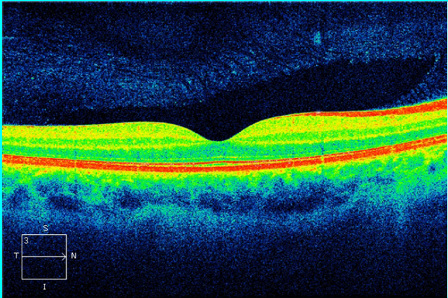

Já a Tomografia de Coerência Óptica ( OCT) é um exame diagnóstico parecido com um ultrassom, que utiliza luz no lugar do som. O exame é não invasivo, não havendo contato com o olho, também indolor. Neste exame é possível verificar a mácula, se está preservada, conforme a foto abaixo.

Pelo OCT é capaz de verificar a qualidade da mácula do paciente